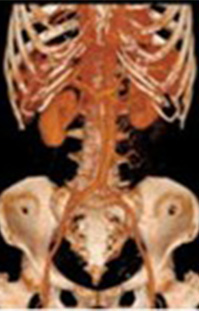

MRI検査室

超電導磁石が埋め込まれたトンネルに体を入れ磁石と電磁波によって体の中の情報を解析し画像にします。いろいろな角度から体の断面を画像化することができ、脳、脊髄、臓器、筋肉、関節、血管などの情報を得ることができます。また、X線を使わないため被ばくの心配がありませんが検査中は大きな音がします。